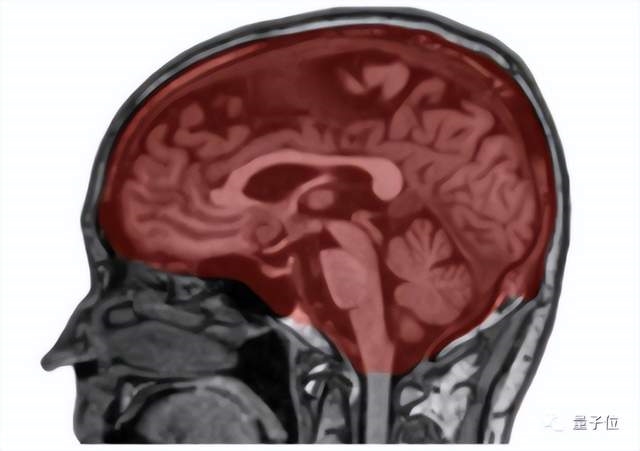

脑区体积也采用了深度学习方法测量,使用FastSurfer卷积神经网络,分割了96个不同的大脑区域。

△脑体积分割结果

考虑到不同参与者头部大小的差异,研究人员还使用了一个单独的深度学习模型来分割颅内容积。

他们手动标注了60名参与者的颅内隔室(头颅内的一系列脑室),然后用这些数据训练医学图像分析深度学习框架nnUNet,用于生成颅内掩膜(覆盖在颅骨内部,包围和保护中枢神经系统的三层薄膜)。